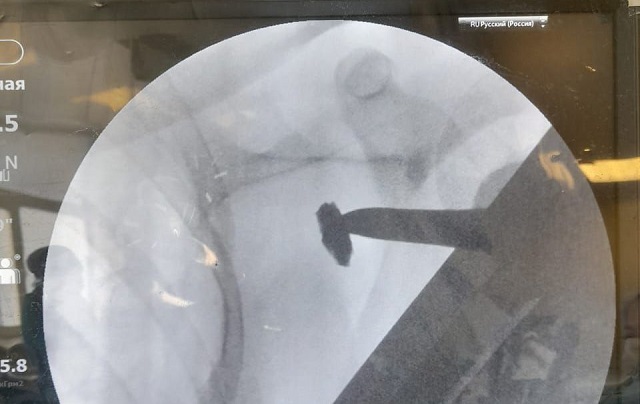

В медучреждении отметили, что подобное хирургическое вмешательство требовало хорошей визуализации, потому его проводили под рентген-аппаратом.

На протяжении всей операции на экране можно было наблюдать, как хирург работает инструментом и скрупулезно ищет осколок. Пациент в это время находился под общим наркозом. В настоящее время боец находится под наблюдением врачей и готовится к выписке.